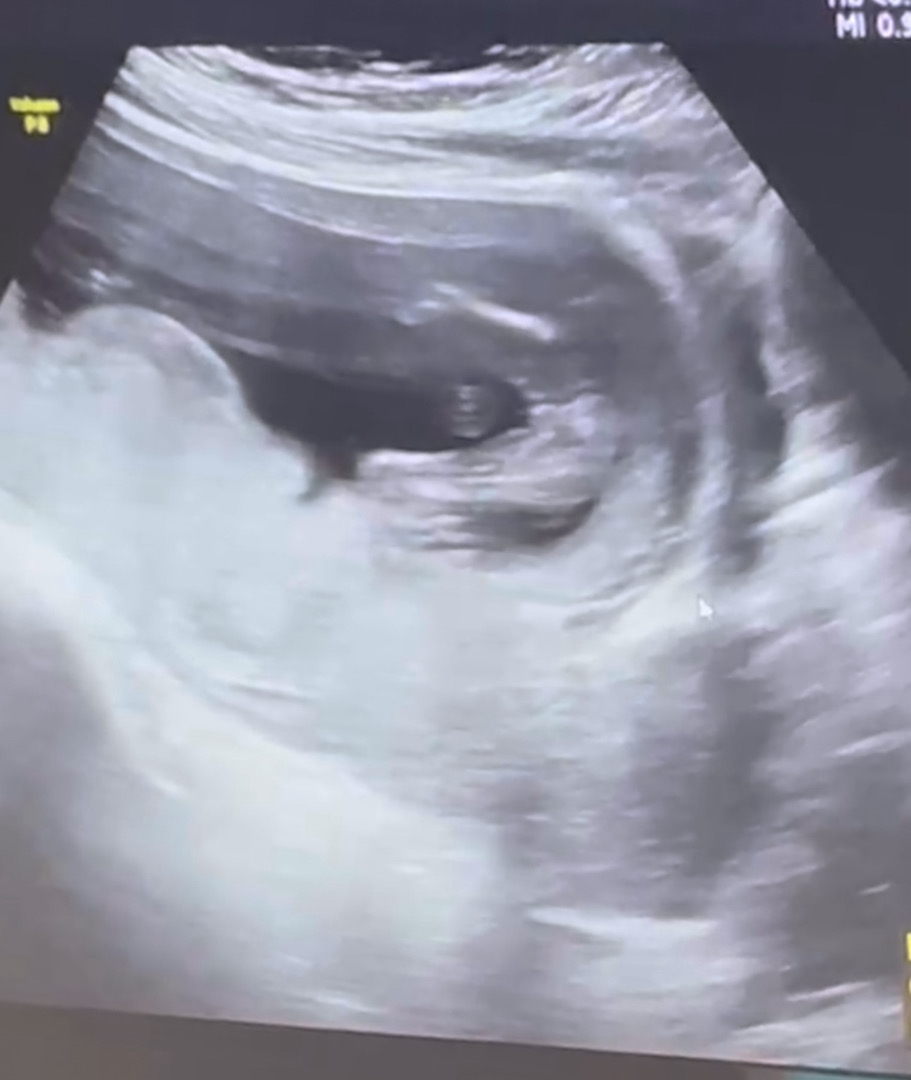

15주 5일 성별반전 있을까요!?

병원에선 확실히 모르겠지만 딸일 가능성이 크다고 하는데 베동님보시기엔 어때보이세요!? 성별 반전 있을까봐 조마조마하네요😂

저 사진 속에서는 반전이 없을 것 같아요

의사선생님께서 더 정확하시겠지만 딸처럼보여요!